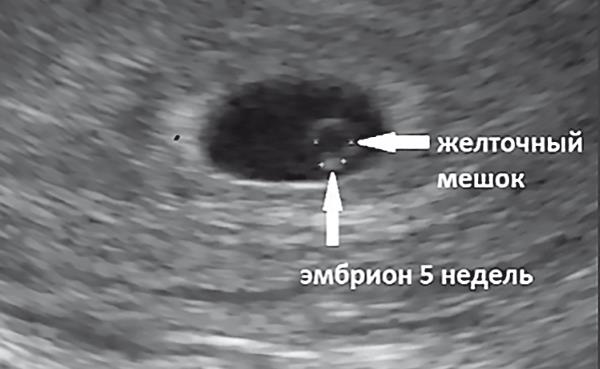

Искусственное прерывание беременностиИзвестно, что жизнь ребенка начинается не с момента рождения, а с момента оплодотворения яйцеклетки (рис. 1.6).

12 недель – максимально допустимый срок, когда искусственное прерывание беременности (аборт) все еще официально разрешено (рис. 1.7).

Рис. 1.6. Ультразвуковое исследование: эмбрион 5 недель